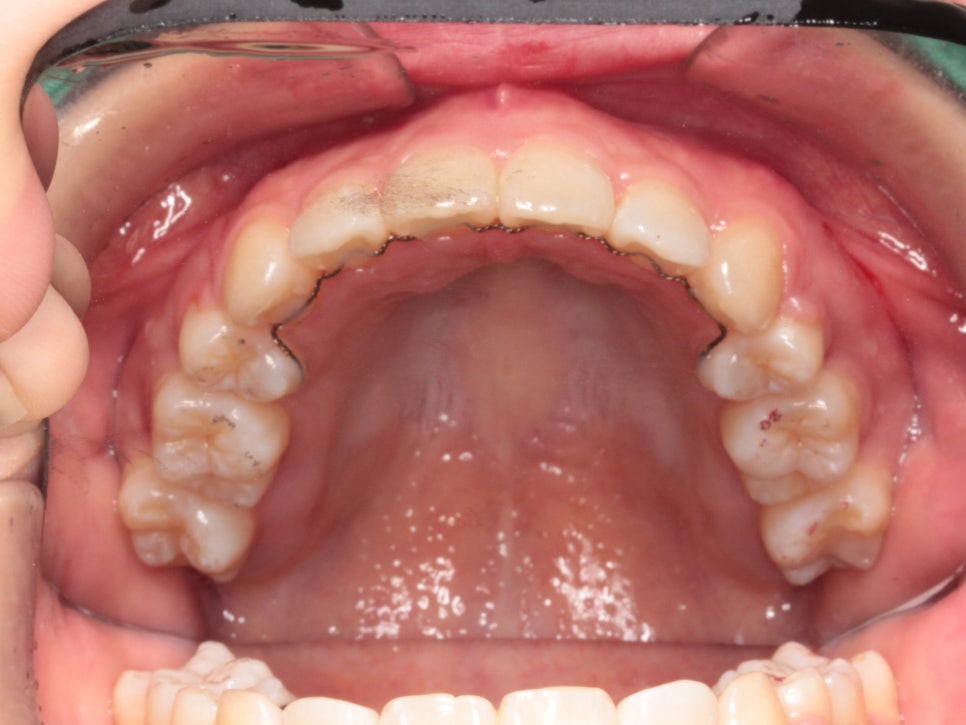

치료방법은 발치를 동반한 미니스크류 교정치료입니다.

미니스크류를 식립 후 바로 찍은 사진입니다.

총 6개의 미니스크류를 식립하고 치료를 했습니다